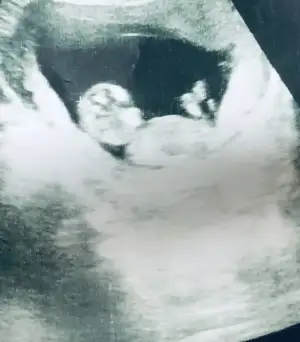

Kızlar burada 11+4 tü doktor önce kiz dedi sonra erkek dedi yorum yapabilir misiniz bana da